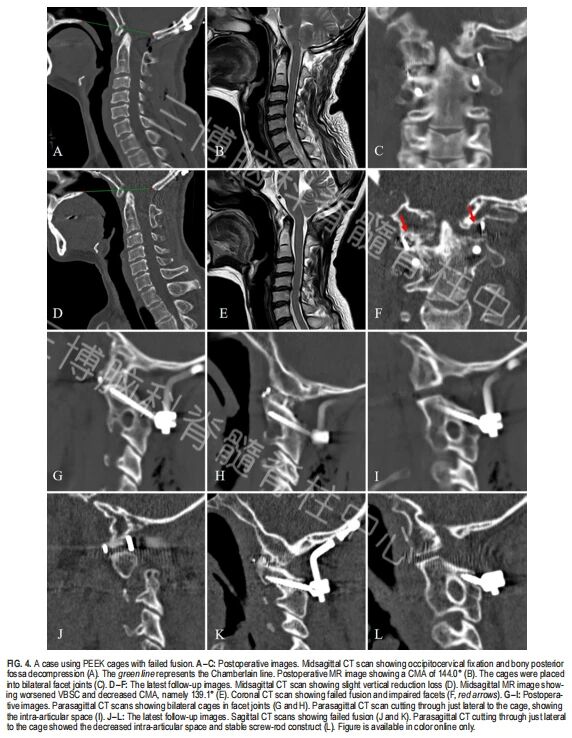

▲图4:一例患者随访过程中出现融合器沉降、垂直复位丢失、延髓颈髓角加重